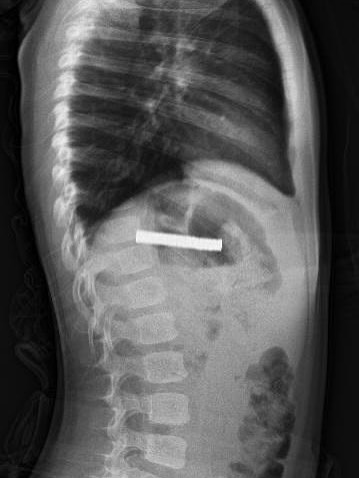

Fırat Üniversitesi Tıp Fakültesi Çocuk Gastroenteroloji, Hepatoloji ve Beslenme Bilim Dalı Başkanı Prof. Dr. Yaşar Doğan ve ekibi tarafından gerçekleştirilen operasyonla, çocuğun yemek borusuna yapışan 19 mıknatıs endoskopik yöntemle çıkarıldı.

Mıknatısların, mide girişinde ve yemek borusunda zedelenmelere yol açtığı belirtildi. Çocuk tedavisinin ardından taburcu edildi.